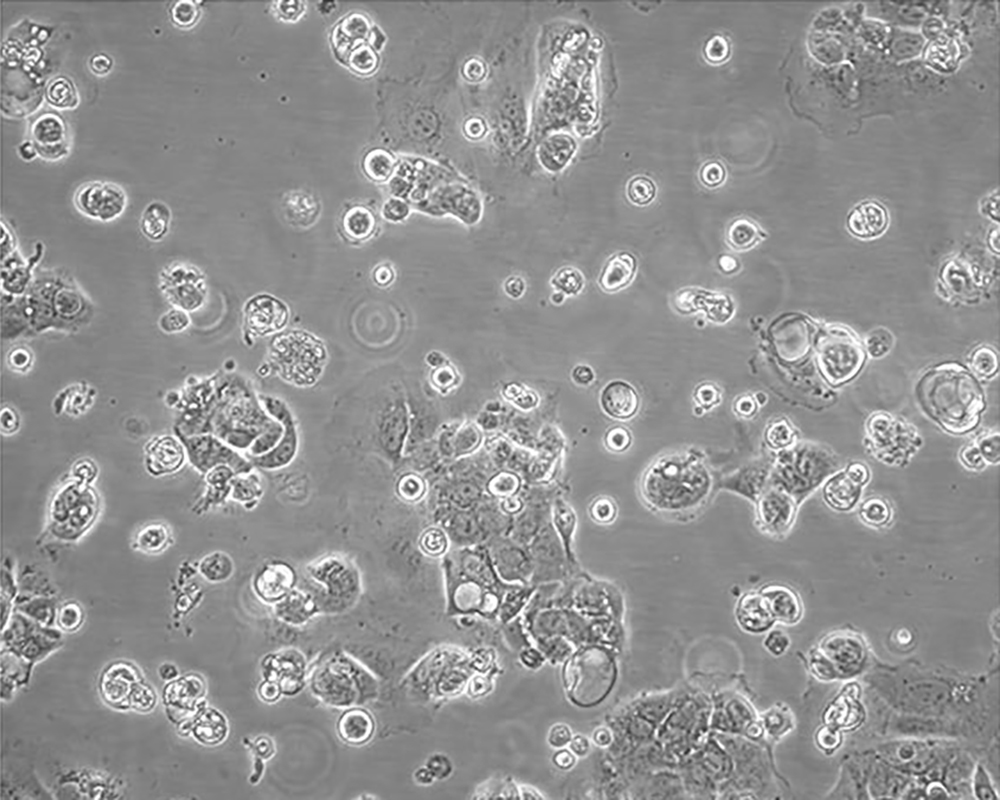

Caco-2

產(chǎn)品名稱 Caco-2

中文名稱 人結(jié)直腸腺癌細胞

組織來源 結(jié)腸腺癌;男性

生長特性 adherent

形態(tài)特征 epithelial

細胞描述 Upon reaching confluence, the cells express characteristics of enterocytic differentiation. Ref Caco-2 cells express retinoic acid binding protein I and retinol binding protein Ⅱ.